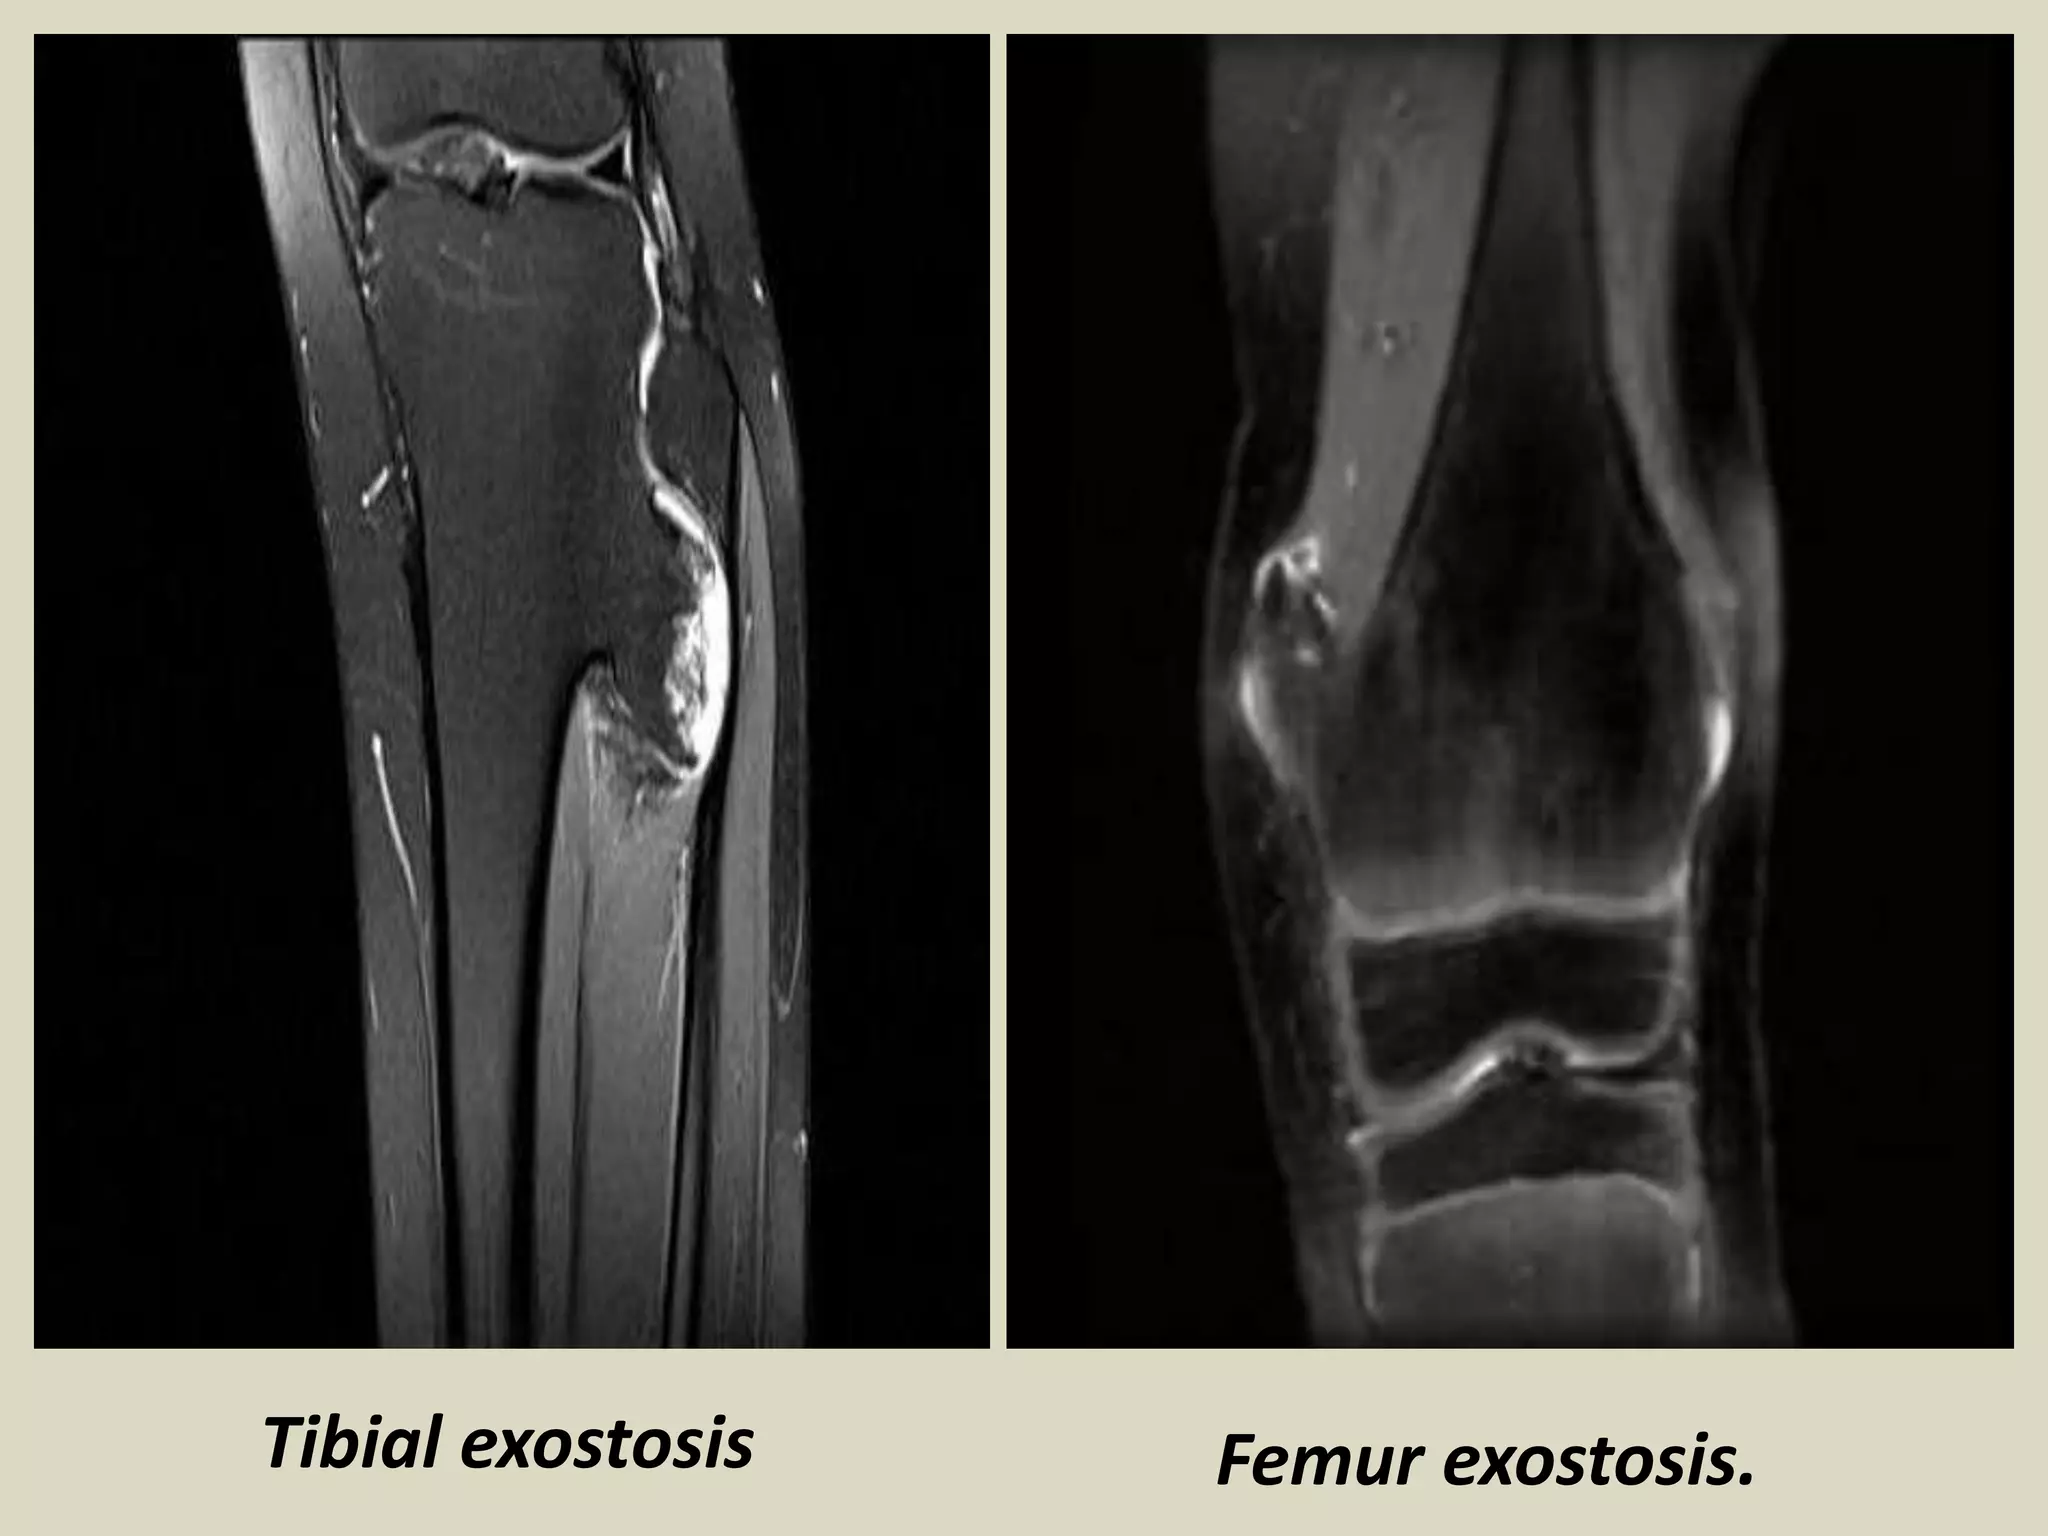

OSTEOCHONDROMA (EXOSTOSIS)

Definition: Cartilage capped bony projection arising on the external surface of bone containing

a marrow cavity that is continuous with that of the underlying bone.

Epidemiology:

-Most common bone tumor.

-Osteochondroma may be solitary or multiple, the latter occurring in the setting of hereditary multiple

exostoses.

-Solitary lesions account for 80% of cases, and most affected patients are diagnosed in their second decade .

- Male preponderance with a male to female ratio 1.5-2:1.

- Hereditary multiple exostoses (HME) is an autosomal dominant genetic disorder, and has prevalence

of 1 per 50 000 in the general population making it one of the more common inherited skeletal disease.

- Patients with HME come to medical attention at the younger age , usually during first decade, because

they cause severe skeletal deformities and are frequently polyostic.

Sites of involvement:

- Generally arise in bones performed by cartilage.

- Most common site of involvement is the metaphyseal region of distal femur, upper humerus, upper tibia

and fibula.

Clinical findings:

- Many, if not most lesions, are asymptomatic and found incidentally. In symptomatic cases, the symptoms

are often related to the size and location of the lesion.

- Most common presentation is that of a hard of long-standing duration.

Imaging:

- Bulbous lesions on X rays, and they a narrow or broad (sessile) osseous radiosense stalk, which is attached

to the underlying bone.

- The characteristic feature is a projection of the cortex in continuity with the underlying bone.

- Excessive cartilage type flocculent calcification should raise the suspicion of malignant transformation.

- CT scan or MRI images typically show continuity of the marrow space into the lesion. A thick cartilaginous

cap rises suspicion of malignant transformation.

Osteochondroma.

Tibial exostosis Femur exostosis.